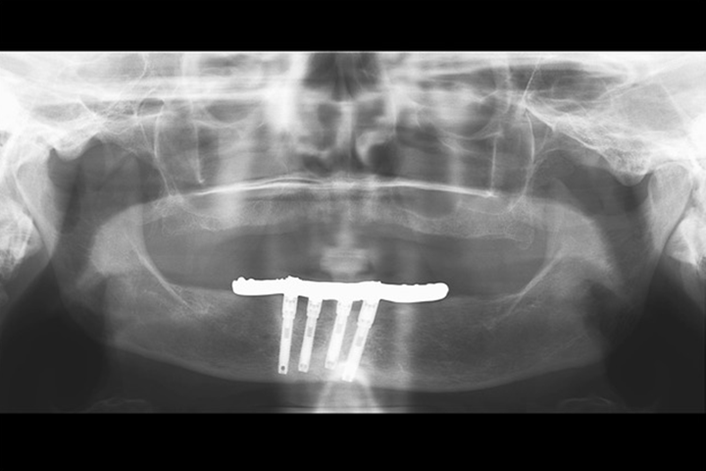

The Journal of Prosthodontics’ sixth annual virtual issue, “Prosthodontic Clinical Reports: Challenging Cases, Novel Technology, Multidisciplinary Treatment,” is now online. The virtual issue compiles 12 clinical reports published in the Journal of Prosthodontics over the last two years.

The articles included in this virtual issue demonstrate the skill, ingenuity, and care prosthodontists provide their patients.They include reports of patients whose microstomia or severe gag reflex make treatment more difficult. One report details a 30-year follow-up so that the reader can see the long-term effects of decisions made over decades of treatment. Novel attachment systems and new materials are tried in some instances. Several of the reports make use of the latest in digital technology.